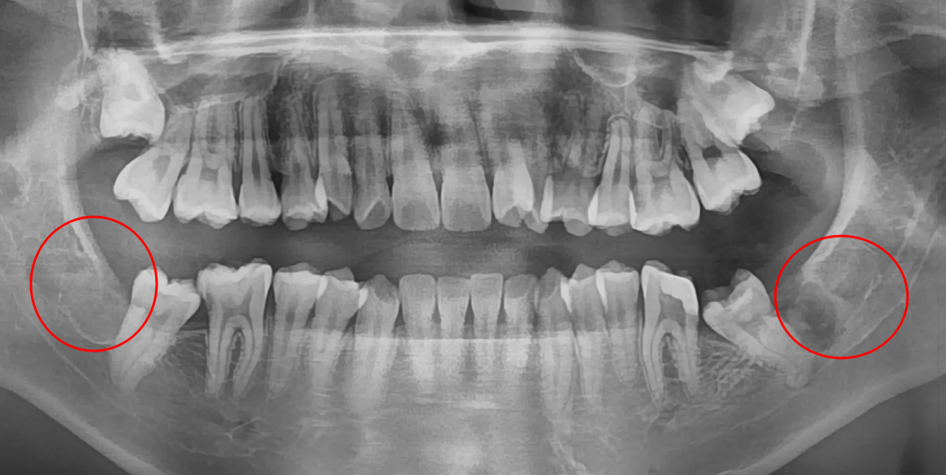

의식하진정마취(수면마취)로

당일 사랑니 4개 발치

발치 전

사랑니 발치 후

검사

결과

20대 여성 환자분으로, 사랑니가 4개 있는 상태로 불편감이 있어 모두 발치를 원하셨습니다.

약 2주 후 출국 예정으로 불가피하게 당일 4개를 모두 발치를 해야 했었습니다. * 일반적으로는 사랑니 4개를 발치 할 때 왼쪽, 오른쪽으로 나누어 최소 1-2주 간 텀을 두고 발치를 합니다.

치료

과정

개수도 많기도 하고, 환자분이 시술 중 통증도 느끼고 싶지 않으셔서

의식하진정마취(수면마취)로 발치를 진행하였고, 통증 없이 치료를 마치셔서 만족하셨습니다.